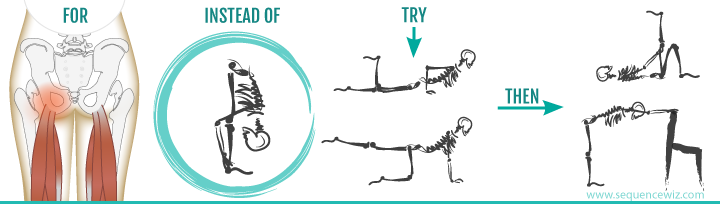

·原因: 疼痛大约在屁股摺痕处。尤其是在你膝盖伸直且将身体向前弯腰时,症状会更明显。这种型态的疼痛表示是连接到骨盆的腘绳肌肌腱受伤,这通常是因为过度的拉扯腘绳肌。(如在瑜伽中:当瑜伽练习者需要保持双腿笔直向前弯曲,然后强迫自己摆姿势时,可能最终会损伤肌腱。)当我们的肌腱受伤,腘绳肌会自然的收缩,试图去保护受伤的肌腱。然而我们认为的是:"腘绳肌紧绷又疼痛,要去伸展它,疼痛自然会消失了",而这样的方式却无法让肌腱修复,反而是重复使其受伤——过度伸展然后再受伤,这样的循环会使复原时间变更长。较好的方式是借由适当地收缩腘绳肌来增加受伤区域的循环,如果可以的话,做简单轻微的伸展。当疼痛急性期结束后,你可以慢慢增加伸展的角度。您的朋友或患者中,是否有人向你这样抱怨过:我的髋部在走路、睡觉时会痛,物理治疗师建议他作核心运动,骨科医师诊断他是梨状肌症候群,也试过请按摩师放松他紧绷的髂胫束。经过仔细的检查后,确认了他疼痛的位置,疼痛的症状都指向无力的外展肌群,造成骨盆位置不良,导致某些肌肉群去代偿。当开始训练他的外展肌群,很快地他的疼痛就不见了。此型态的疼痛通常会出现在臀部外侧或上侧,可能会向下至大腿的外侧。它通常是在散步跟晚上侧躺在患侧时更糟。薄弱的外展肌群,紧绷的髂胫束可能是引起疼痛的一种因素。这种疼痛常被认为是髂胫束的问题,所以借由伸展髂胫束,或用滚筒去放松,这会非常有效,但并没有解决问题的根源-外展肌无力,除非你去加强肌力,否则问题会一再出现。你需要锻炼你的髋外展肌,可以利用单脚站,另一侧大腿对抗重力做髋外展动作,两侧轮流施行,让髋外展肌做为稳定以及动作的功能角色。大家知道坐骨神经分布的范围到底有多大吗?它是你的身体里最长的一条神经,从下段脊椎一路延伸到脚,而且它也非常的粗,大概就像是你的小指头一样粗,穿过你的脊椎与髋关节。因为这条神经粗又长,它可能在很多地方被挤压到,而造成类似坐骨神经痛的症状。两个常见被挤压位置在下背部(腰椎椎体间)跟紧绷的梨状肌下面。梨状肌是一条很小的肌肉,当它太紧绷时可能会造成很多困扰。它位于髋部深处,在髋关节弯曲状态下,负责带动髋关节外转跟外展。紧绷的梨状肌会造成屁股痛,但当它压迫到通过梨状肌下面的坐骨神经时,就会使情况变得更糟。疼痛通常会出现在臀部中间的位置、下背部,或任何坐骨神经通过的地方。症状也有可能是脚麻或无力。如果是因为椎间盘突出引起的坐骨神经痛,是比较大的问题,超过我们本篇所要介绍的范围,在物理治疗师的指导下,加强核心肌群的运动是个不错的方式。如果疼痛是因为紧绷的梨状肌,我们可以着手于放松紧绷的肌肉。·较好的方式:利用我们常见的”收缩-放松-伸展原则”(Contract-Relax-Stretch principle)步骤①:从收缩周围肌肉开始(尤其是臀大肌),来增加此区域的血液循环。步骤②:然后我们可以轻轻的收缩梨状肌 (contract the piriformis ),让它慢慢放松掉原本慢性的收缩(如果不会感到疼痛),搭配温和的伸展。我们可以借鉴瑜伽中的动作,像是勇者式二(Virabhadrasana 2)、侧三角伸展式(Utthita Parsvakonasana)跟蚌蛤式都可以让梨状肌收缩,而在站姿下利用椅子做扭转动作,以及半鱼王式(Ardha Matsyendrasana)是伸展梨状肌最好的选择,因为此姿势会让你的脚处于弯曲、内收,但不会外转的姿势,这对于梨状肌是比较温和的姿势。步骤③:当你觉得你已经准备好在伸展加入外转的动作时,你可以选择穿针引线式(Thread-the-needle pose)来取代鸽式(Pigeon)或牛面式(Gomukasana),这会让使梨状肌受到较小的力矩。当你练习这些动作后,你就可以试着做鸽式(Pigeon)或牛面式(Gomukasana)。PS:但有些学生即使练习很久也还是没办法完成鸽式或牛面式。此外,由于过紧的内收肌群会使髋关节呈现内转姿势,使梨状肌产生额外的压力进而压迫到神经,所以也可使用相同的方式来舒缓内收肌群的慢性紧缩。紧绷的腘绳肌也会造成坐骨神经受压迫,所以对于缓解此肌群的张力也是很有效果的。请记住,即使最简易的腘绳肌伸展运动也可能造成一位有坐骨神经痛症状的人极大地疼痛,所以建议用前面提及到第一种臀部疼痛的腘绳肌伸展原则。 请记住,一个疼痛症状,有可能是许多原因造成的。如果您的疼痛在你经过一番努力后,仍然存在,应该是要去寻求专业建议的时候了。